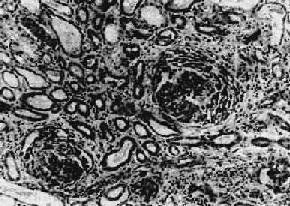

主要病变为肾小球系膜细胞和基质增生,系膜区增宽(图12-10,图12-11)。毛细血管壁无明显变化,管腔通畅。系膜内可有少数单核细胞和中性粒细胞浸润。病变严重者可引起系膜硬化。

图12-10 弥漫性系膜增生性肾小球肾炎

肾小球系膜区略增宽,系膜细胞数量增多